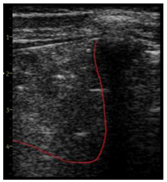

| LUS Score | 0 Points | 1 Point | 2 Points | 3 Points |

|---|---|---|---|---|

| Image |  |  |  |  |

| Description of image | Normal or physiological pattern displaying A-lines (right part), along with two sparse B-lines (yellow arrows) per intercostal space | Three sparse B-lines (yellow arrows) per intercostal space, accompanied by pleural abnormalities, such as irregularities or thickening (orange circle) | Small peripheral consolidations smaller than 1 cm (red dotted area), a small area with ‘white-lung’ appearance, adjacent coalescent or merging B-lines | Substantial peripheral consolidations (marked with red) wider than 1 cm with the presence of air bronchograms (hyperechoic areas inside); the image is from an infant with bacterial pneumonia not included in this study |